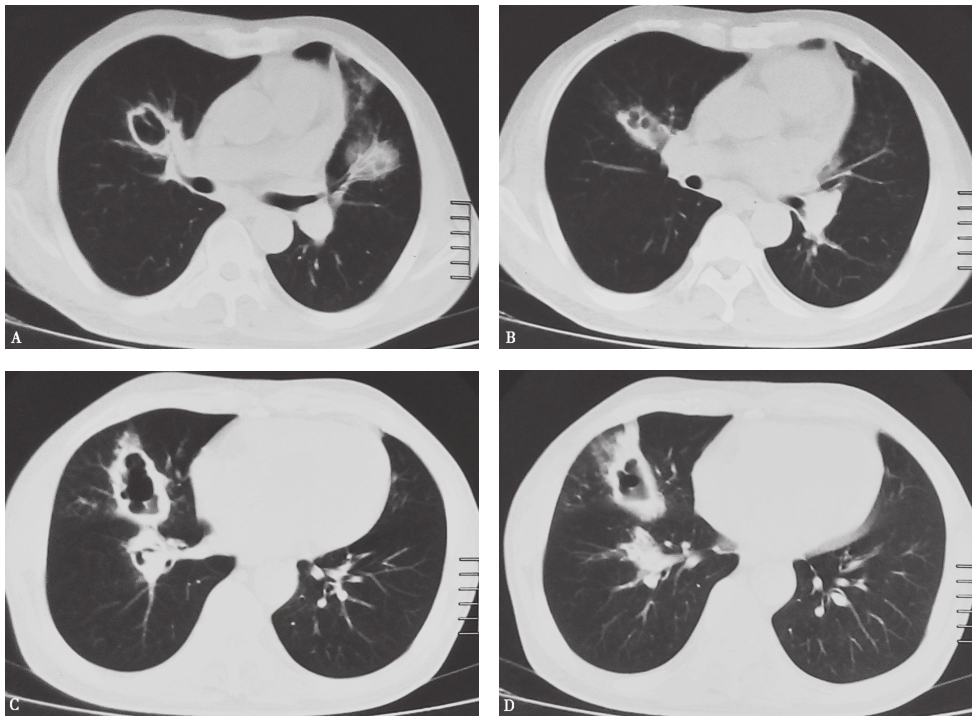

入院前两次胸部CT表现见图1、图2。

图1 发病第20天胸部CT表现

胸部CT可见双肺片状高密度影及多发空洞形成,伴右肺中叶膨胀不全

图2 发病第32天胸部CT表现

胸部CT可见右肺中叶区不张,左肺上叶原空洞部位出现部分实变

4.影像学可见双肺多发片状密度增高影,伴有空洞形成,且短时间内影像学改变明显,由多发斑片影发展为多发空洞,继而出现局部肺不张及实变。